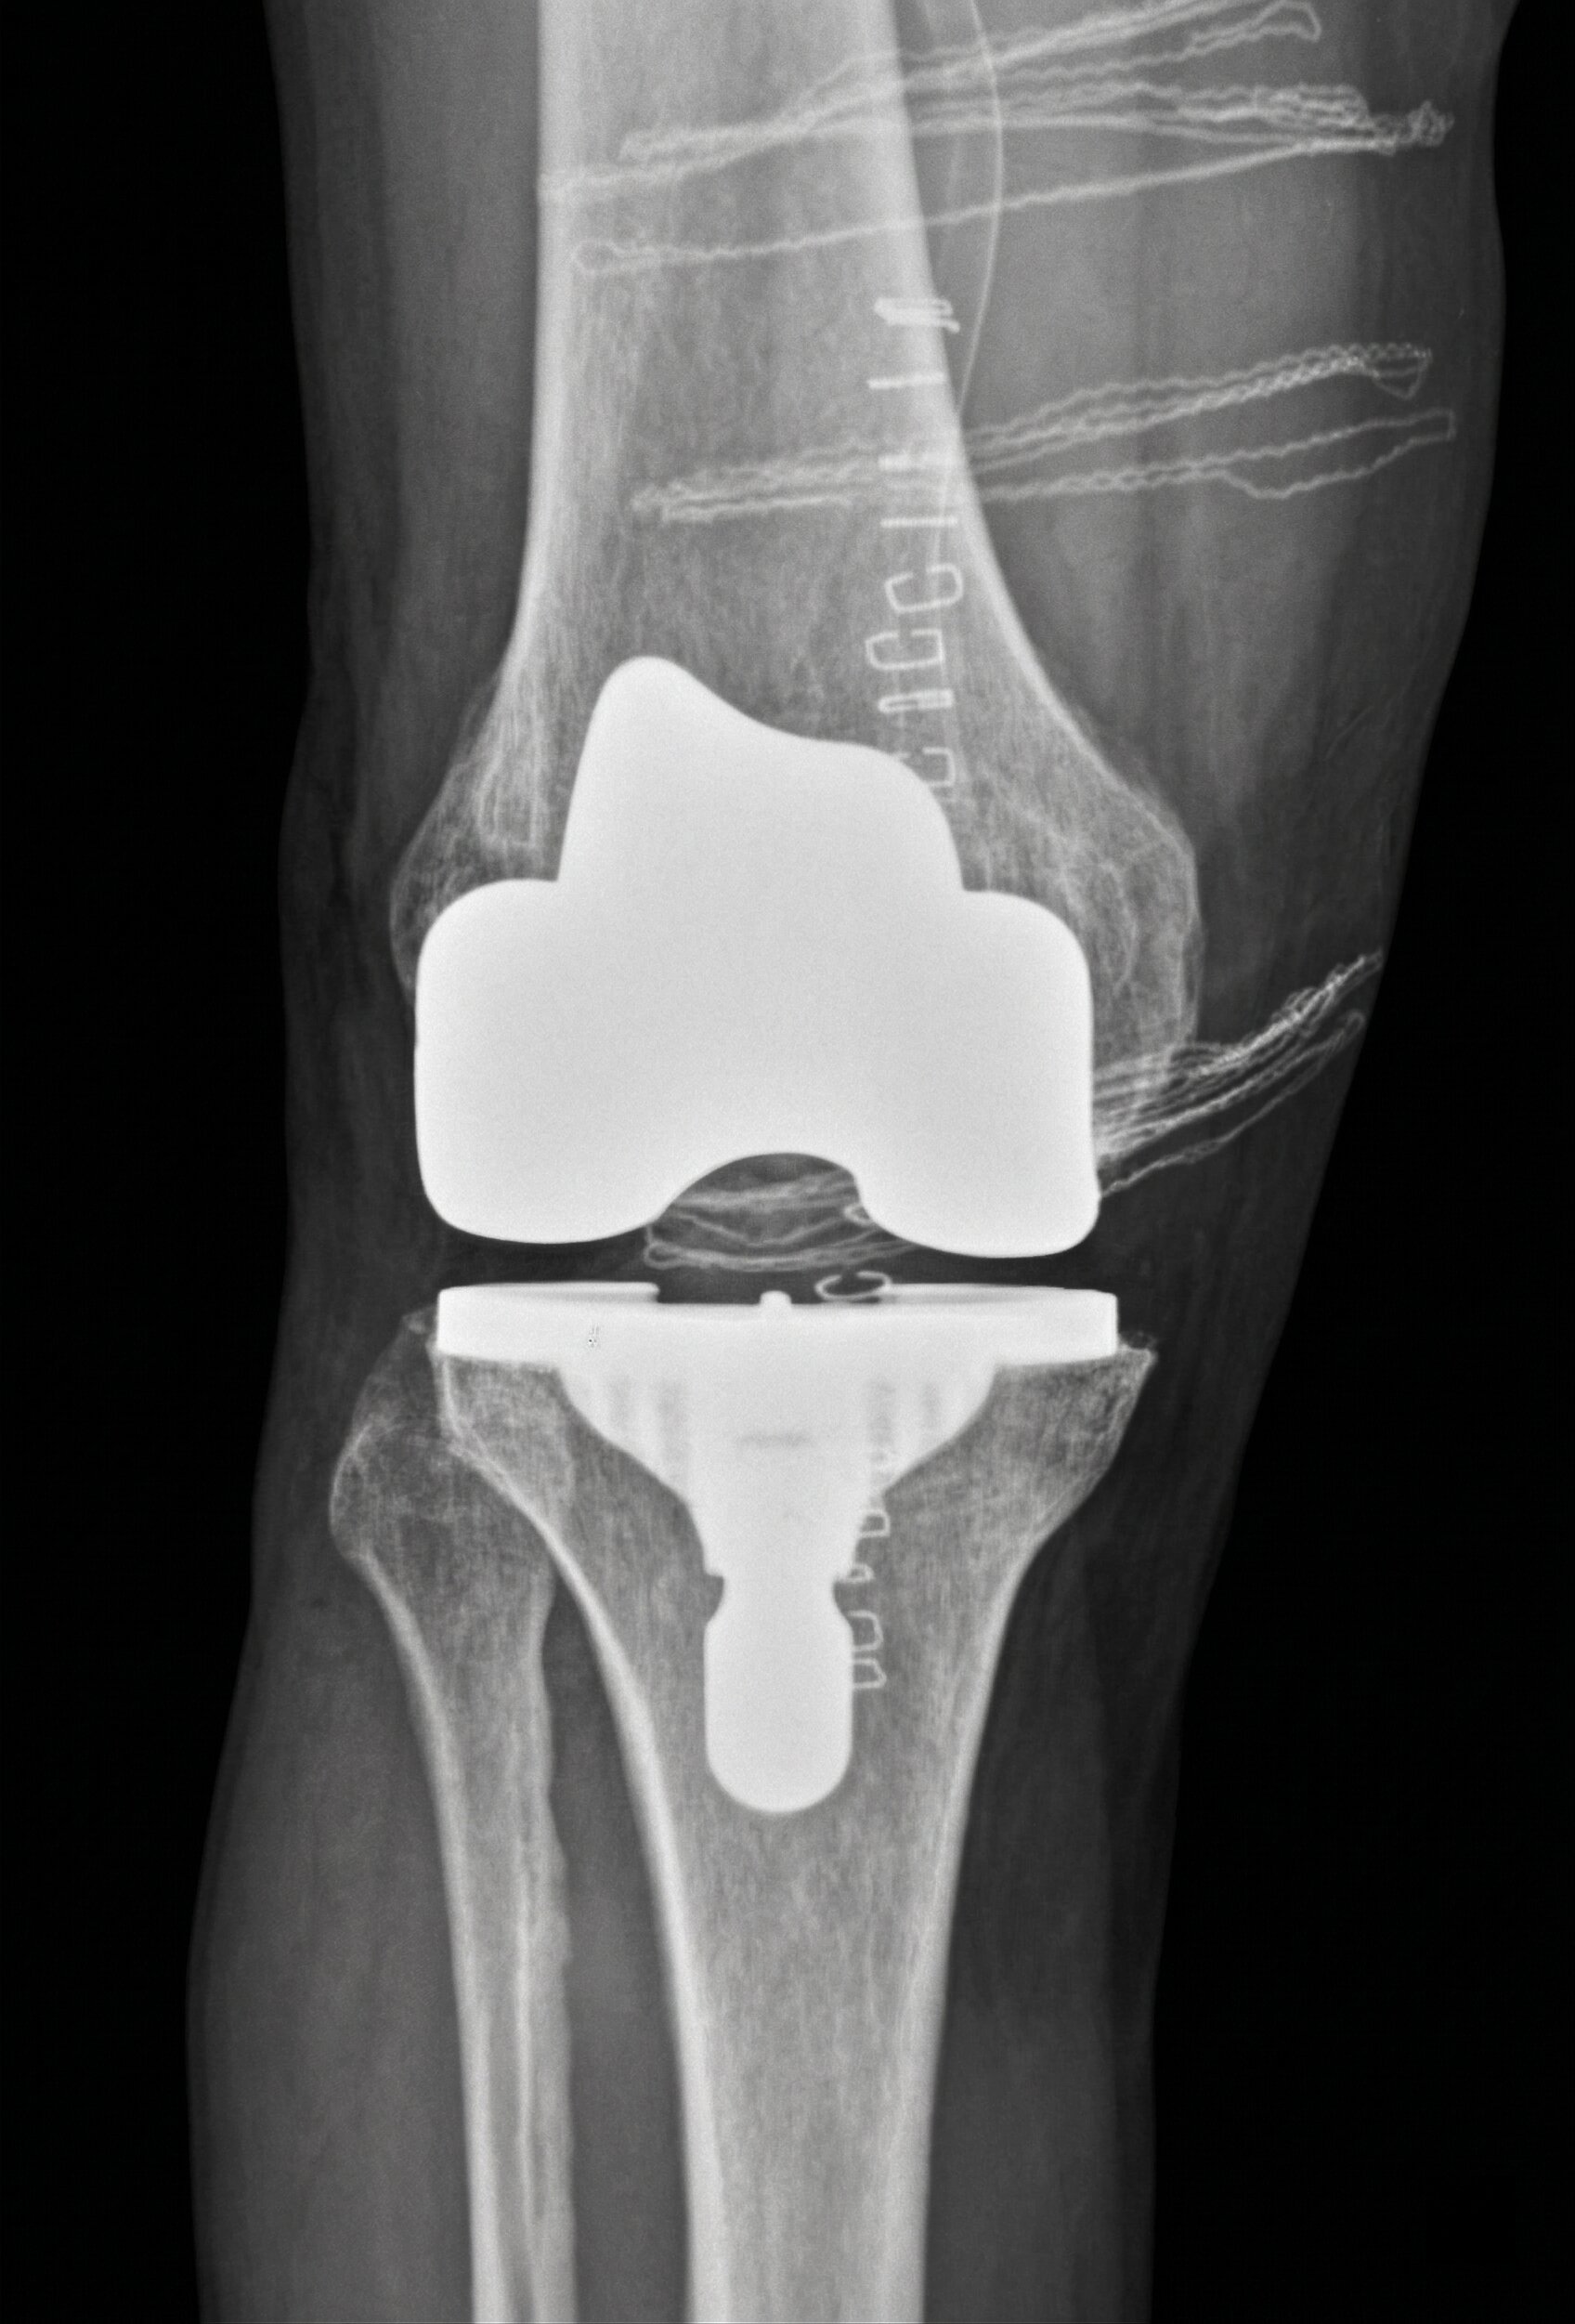

Quando le terapie conservative non sono più efficaci, si esegue protesi totale o parziale.